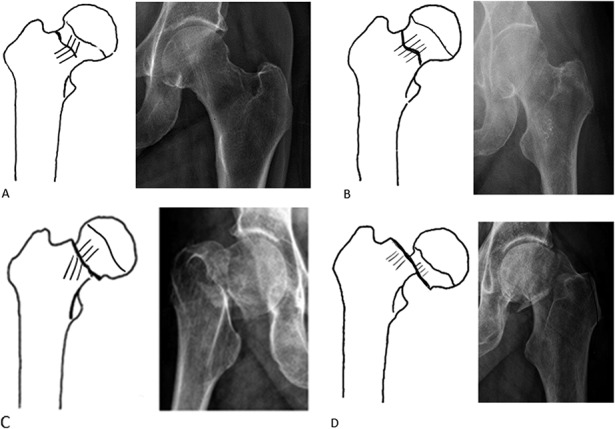

Classification de Vancouver pour les fractures périprothétiques

- A : région trochantérienne

- AG : grand trochanter ;

- AL : petit trochanter ;

- B : autour ou juste distalement à la tige

- B1 : tige fixée ;

- B2 : tige descellée ;

- B3 : tige descellée et qualité osseuse inadéquate ;

- C : bien distalement à la tige.